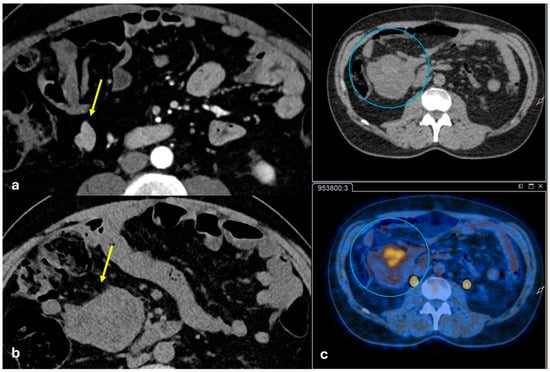

3.1.5. Peritoneal Lymphomatosis

3.1.6. Mesenteric Metastases from Ileal Neuroendocrine (Carcinoid) Tumors